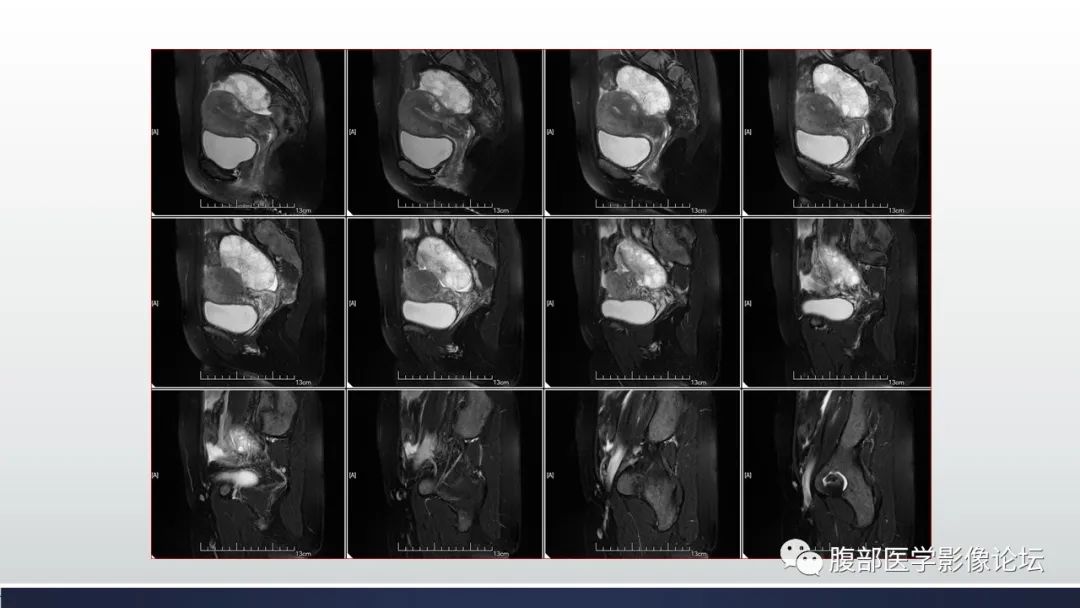

【病例】子宫内膜透明细胞癌1例MR-13

【病例】子宫内膜透明细胞癌1例MR-14

【病例】子宫内膜透明细胞癌1例MR-15

【病例】子宫内膜透明细胞癌1例MR-16